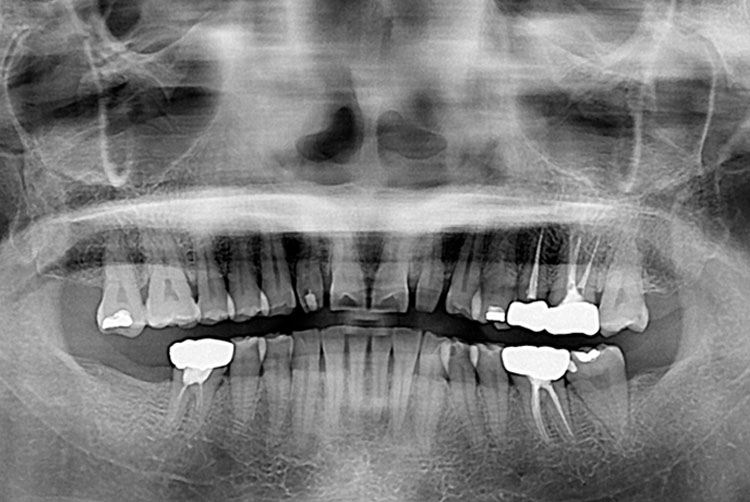

[임플란트] 임플란트

치료전 : 2016-07-14

세종치과는 많은 환자와 다양한 케이스를 바탕으로 항상 편안한 임플란트 수술을 제공하고자 노력하고,

오래동안 튼튼히 쓸 수 있는 임플란트 수술을 가장 큰 목표로 삼고 있습니다.